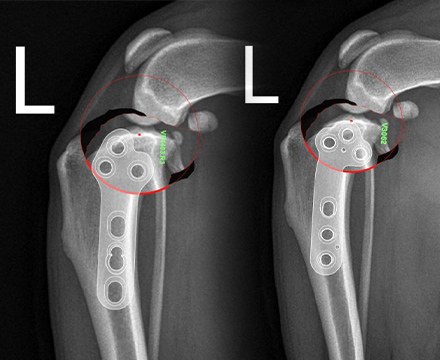

V-pop 프로그램을 이용한

세심한 수술 계획,

수술 중 발생할 수 있는 변수 조절

예은동물의료센터는 V-pop 프로그램을 이용하여 세심한 수술 계획을 세우고 수술 중 발생할 수 있는 변수 조절합니다.

또한 다양한 정형외과 회사 제품 보유로 환자 맞춤 수술 가능합니다.

다양한 크기/다양한 뼈 모양에 가능한 기구 보유하여 리허설을 통해서 환자에게 가장 적합한 플레이트 이용합니다.

Synthes plate vs fixin plate

fixin plate vs jeil medial plate

- 다양한 정형외과 회사 제품 보유로 환자 맞춤 수술 가능

- 다양한 크기/다양한 뼈 모양에 가능한 기구 보유

- 리허설을 통해서 환자에게 가장 적합한 플레이트 이용

보유 회사 제품: Fixin, Jeil Medical, Vi, Synthes